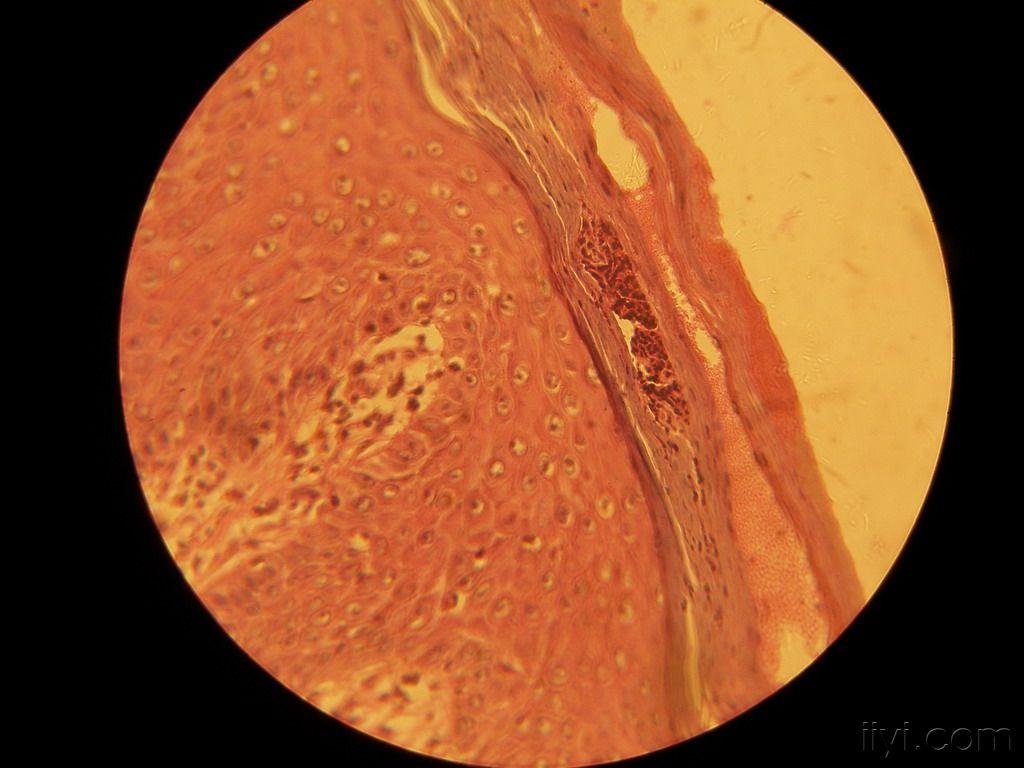

寻常型银屑病一例

图片尺寸640x480